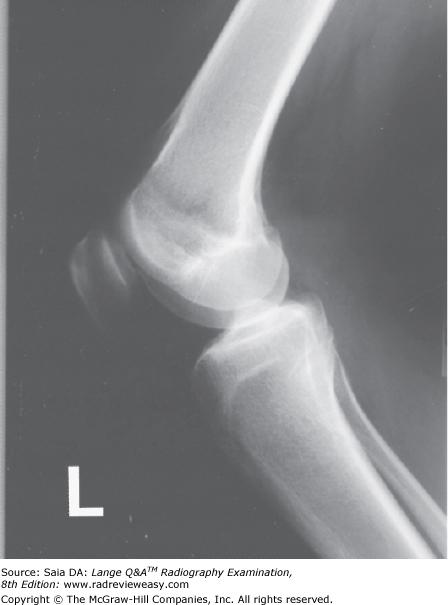

All elbow fat pads are best demonstrated in which position?

A AP

B Lateral

C Acute flexion

D AP partial flexion

-There are three important fat pads associated with the elbow. The anterior fat pad is located just anterior to the distal humerus. The posterior fat pad is located within the olecranon fossa at the distal posterior humerus. The supinator fat pad/stripe is located at the proximal radius just anterior to the head, neck, and tuberosity. The posterior fat pad is not visible radiographically in the normal elbow. All three fat pads can be demonstrated only in the lateral projection of the elbow.